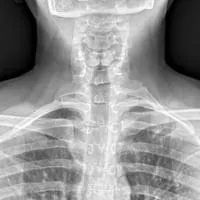

X-rays show excellent bone detail, but do not show soft tissue detail, and are limited to two dimensions. X-rays do not show arteries or veins. About 1% of the population has cervical ribs, but most of these people do not have arterial TOS. Even in patients with cervical ribs and arterial TOS, they have had cervical ribs their entire life, and only developed arterial TOS when they become symptomatic. X-rays thus have quite limited value in diagnosing arterial TOS and in planning treatment.